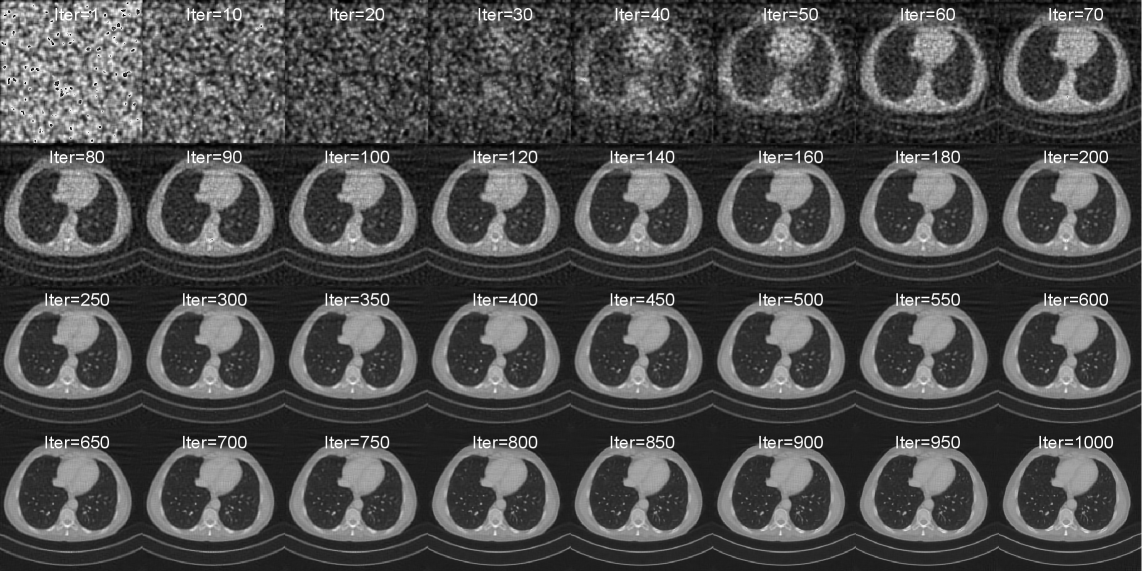

Figure 4: This figure illustrates the reconstruction process by iterations of Fan-Beam 60-view CT. The positions of Gaussians are initialized using Filtered Back Projection, as described in the experimental settings.

Figures 4, 5, and 6 visually depict the reconstruction process across various iterations, with the corresponding iteration number indicated for each image. For comparative purposes, Gaussians for Sparse-View CT are initialized as detailed in the main text, whereas those for Limited-Angle CT are initialized randomly. As the iterations progress, the reconstructed volumes consistently show steady improvement, demonstrating the effectiveness of DGR.